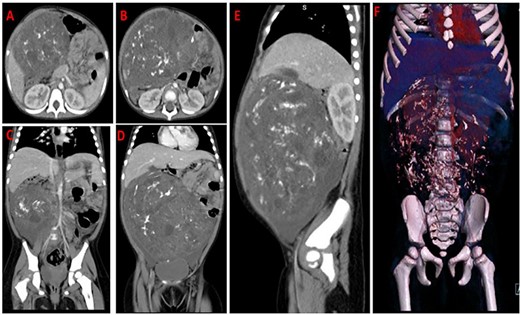

Chest x-ray (Fig. 1) was normal, while abdominal computed tomography (CT) scan showed a huge well-defined heterogenous mass arising from the peritoneal cavity measuring 10.3 cm (AP) × 16.2 cm (T) × 16.7 cm (CC) with central and peripheral calcifications, (Fig. 2). The tumor had pressure effect on the bowels, pancreas and right kidney. The child underwent an elective laparotomy where intraoperatively amber colored ascites was found and a huge left ovarian mass that was free and not adherent to adjacent structures. Left sided salpingo-ophorectomy was done removing the whole mass (Fig. 3) and was sent for histopathology analysis. The uterus, right ovary and fallopian tube were essentially unremarkable. Histopathology of the specimen highlighted a variety of immature and mature tissues derived from the three germ layers (Fig. 4 A–C); whereas a minimal panel of immunohistochemical staining demonstrated strong positivity of the tumor cells for S100 and Neuron specific enolase antibodies (Fig. 4D); thus confirming the diagnosis of immature teratoma, low grade (Grade I), pT2cN0M0. After establishing the diagnosis, the child was reviewed in tumor board by a multidisciplinary team of experts. She recovered well and was discharged on the fourth day postoperatively post discharge; the child attended our pediatric oncology clinic with no any new complaints. She was followed-up with serum chorionic gonadotropin (HCG) and alpha-feto protein (AFP) tests which were within normal during the two monthly visits.

CT-scan images of axial (A,B), coronal (C,D), sagittal contrasted abdomen (E) and 3D virtual reconstruction (F); showing a large heterogenous mass occupying the abdomen and pelvis with mixed fat and soft tissue density and intratumoral calcifications displacing the air filled bowels to the left side.